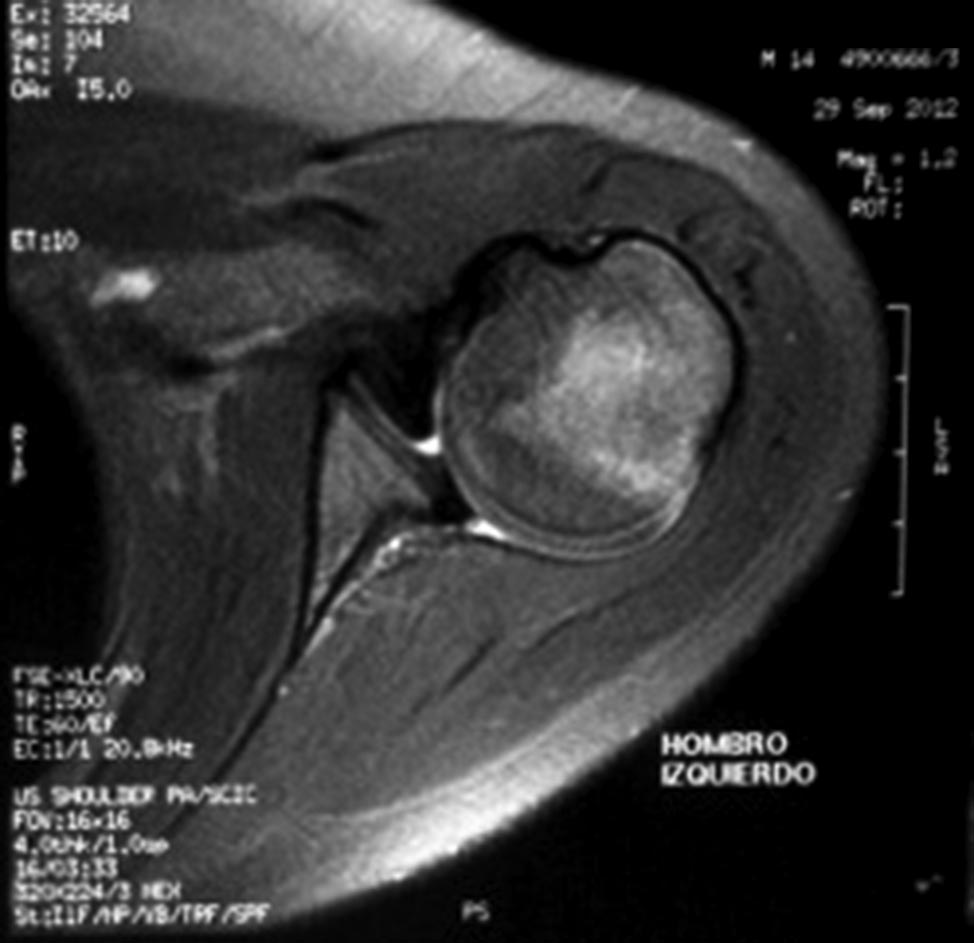

La RNM, se observa la cabeza del humero en rotación interna y en luxación posterior (fig. 1).

Figura 1: RNM posterior a la lesión, muestra la inestabilidad posterior

No se evidencia lesión ósea ni en glena ni en humero.

En sector posterior de glena vemos el decolamiento, la avulsión capsular posterior, es difícil valorar la integridad del rodete glenoideo posterior.

En el sector anterior a la cabeza humeral, el subescapular acompaña el desplazamiento posterior de la cabeza, acodándose en el espacio articular pero no muestra una lesión identificable (fig. 1).